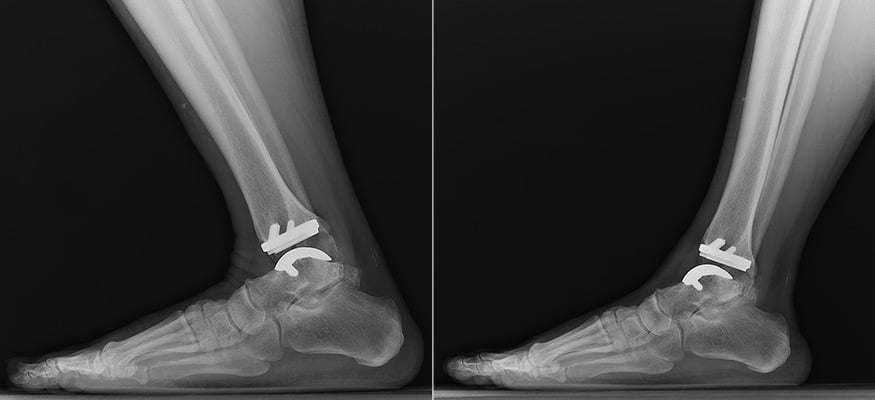

X-rays showing a patient flexing and extending their ankle after replacement.